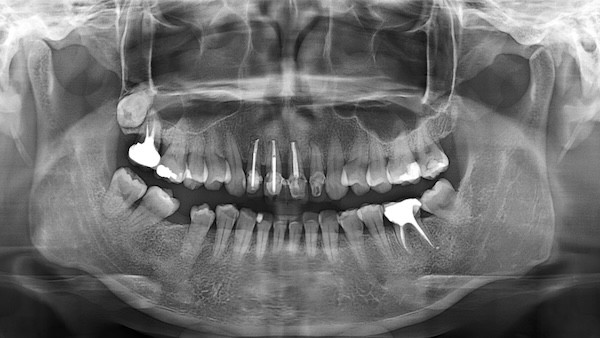

Before

上顎前牙區骨質較薄,使前牙植牙技術難度極高。檢查發現謝小姐骨質嚴重萎縮,必須先補骨以重建足夠骨量,確保植牙長期穩固。江院長形容,補骨就像打地基,不穩固便可能導致骨流失與植體鬆動。

此外,謝小姐意外後牙齦萎縮,直接裝假牙會影響美觀與成功率。江院長指出,補肉手術不僅為美觀,更攸關植牙成功率,適當角化能延長植牙使用年限。因此,他在植牙同時為謝小姐進行牙齦美容補肉,讓牙齦恢復豐盈,締造出堅實又自然的笑容。